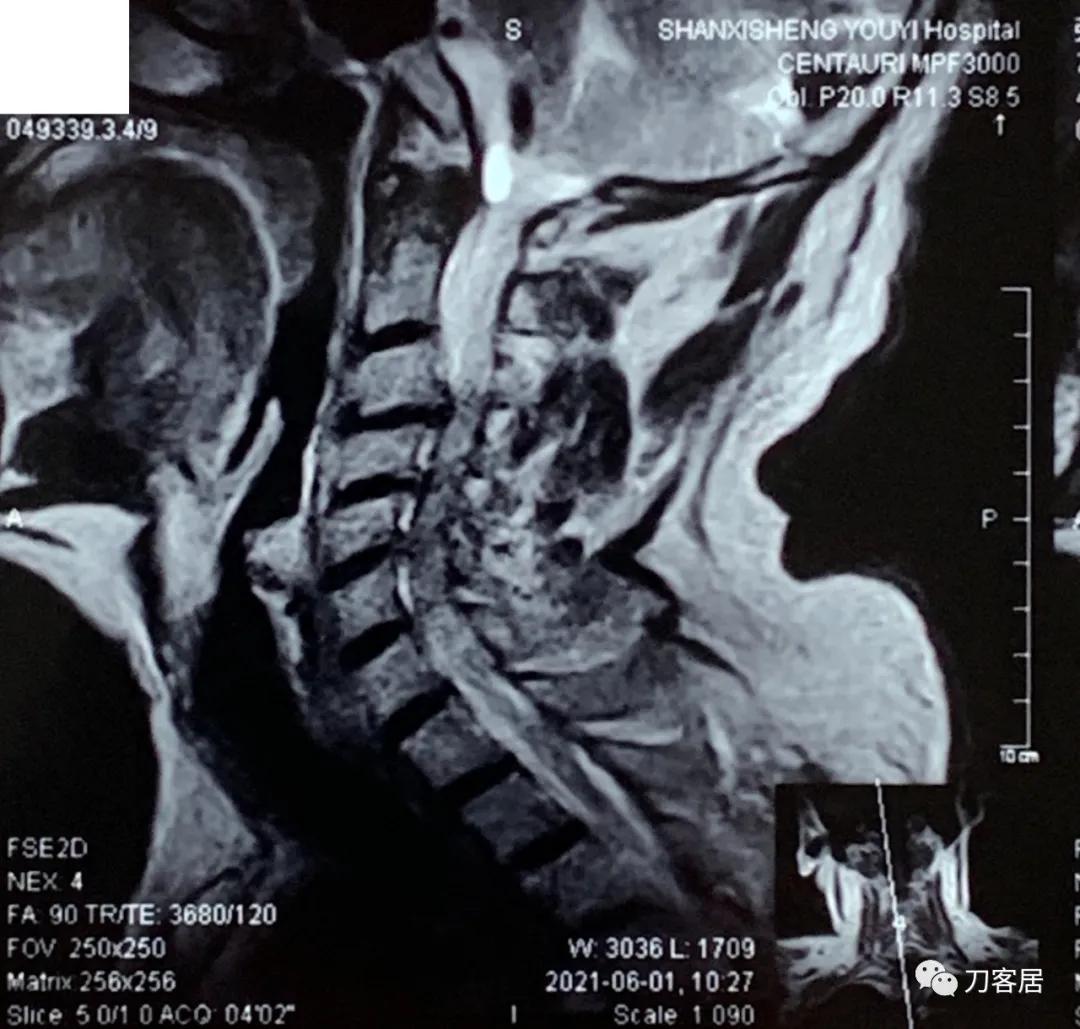

自带颈椎MRI提示颈3-4,颈4-5,颈5-6,颈6-7椎间盘突出,椎管狭窄。目前无明确上位神经损伤表现,暂不处理。骨密度提示骨量减少,但因患者的临床表现,符合骨质疏松症的表现,夜间痛明显,活动后缓解,且已高龄,虽然患者的颈椎MRI片子显示多节段椎间盘突出,椎管狭窄,比较严重, 但无明确的神经损伤表现,病理反射阴性,所以,选择保守治疗,先行抗骨质疏松,以观疗效后决定是否在未来需要手术治疗。

诊断: 骨质疏松症,颈3-7椎间盘突出,颈椎管狭窄。

2021年6月1日外院的颈椎MRI